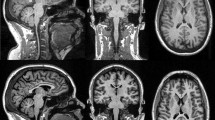

For clinical purposes and research projects in neurological disease, it is of interest to evaluate the performance and comparability of available sequences and software packages for brain volume assessment to determine whether they provide equivalent results. This study compares cross-sectional brain volume values derived from images obtained with MP-RAGE or MP2RAGE sequences, using SIENA/X, SPM, or MorphoBox.

MP-RAGE and MP2RAGE T1-weighted images were obtained from 24 healthy volunteers. Back-to-back scans were performed in 12 of them. Brain volumes, coefficients of variation, and concordance coefficients were determined.

Significant differences were found for most brain volumes derived from MP-RAGE and MP2RAGE images. MP2RAGE-derived measures showed a non-significant trend to larger coefficients of variation. There were statistical differences between brain volumes determined with the three software packages, whereas coefficients of variation were comparable for most brain volumes. Correlation and concordance values were lower for CSF and brain parenchyma fraction measures.

The results obtained advise caution when comparing brain volumes obtained by different sequences and software packages. Of note, for most brain volume measures, the MP2RAGE and MorphoBox coefficients of variation were similar to those obtained with MP-RAGE, SIENA/X or SPM, accepted tools for clinical research.